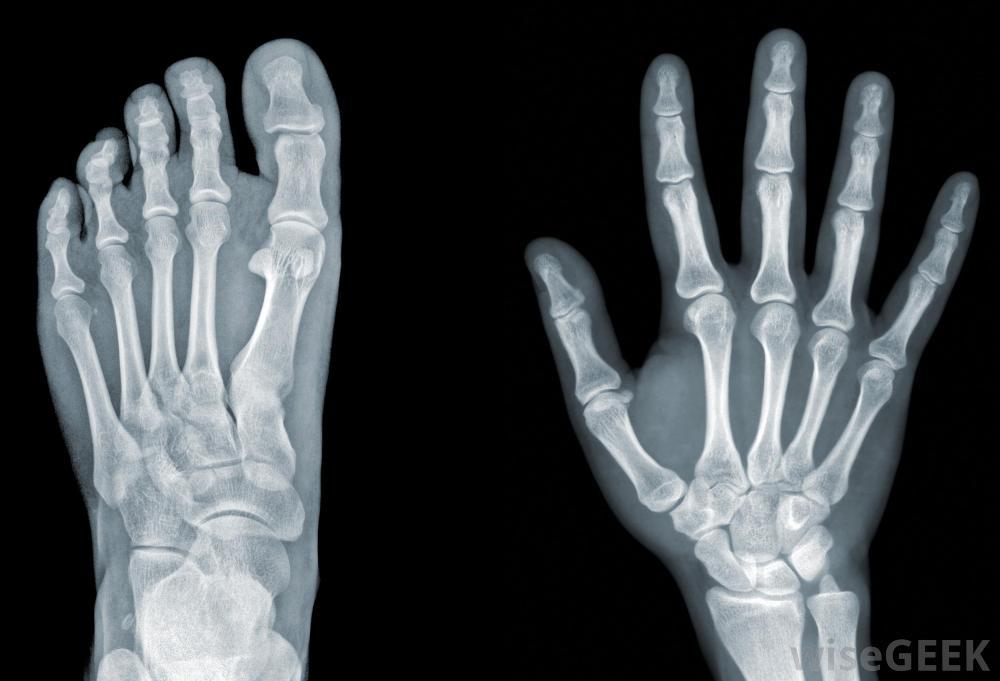

1. How it works

1. Creates pictures of the inside of your body in different shades of black and white. Different tissues absorb different amounts of radiation leading to the varying shades of gray shown on an x-ray

1. Dense areas of the body that don't allow much of the x-rays to pass through appear white (bones) as opposed to hollow or air filled places of the body that appear black (lungs)

2. What it shows

1. Bones, joint spaces, the heart, (size/shape), changes in density, and fluid collection

2. Normal foot and hand x-ray